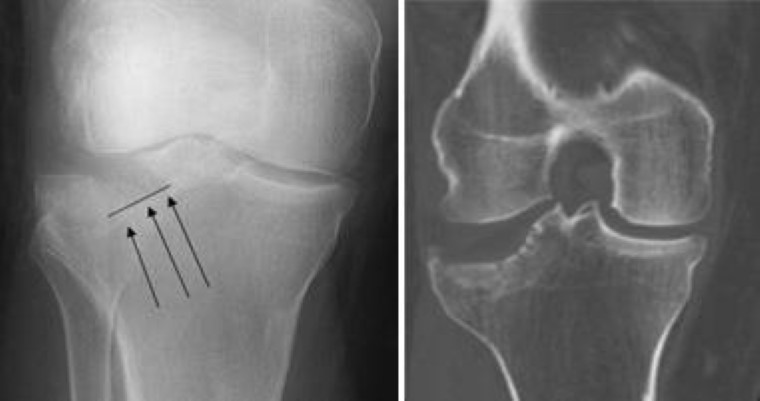

X-ray and CT scan of proximal tibia fracture

Doctors often use both X-rays (Left) and CT scans (Right) to determine the location and displacement of the fragments of broken bone.

• X-rays. The most common way to evaluate a fracture is with X-rays, which provide clear images of bone. X-rays can show whether a bone is intact or broken. They can also show the type of fracture and where it is located within the tibia.

• Computerized tomography (CT) scan. A CT scan shows more detail about your fracture. It can provide your doctor with valuable information about the severity of the fracture and help your doctor decide if and how to fix the break.